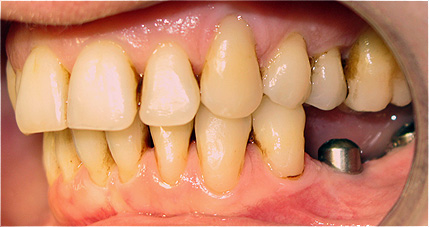

Caso 3 - Desdentado total reabilitado com prótese acrílica removível inferior, barra e clips para retenção e estabilidade

![]() |

![]() ![]() |